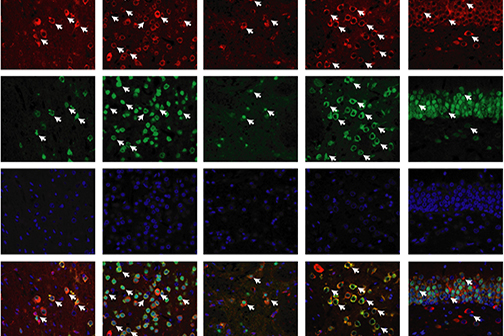

LSU Health New Orleans Discovery May Complement Recovery from Ischemic Stroke

A study led by Nicolas Bazan, MD, PhD, Director of the LSU Health New Orleans Neuroscience Center, pinpointed which cells within specific areas of the brain are involved in post-stroke response and found that the delivery of precursors of Elovanoids, a class of molecules that synchronize cell-to-cell communication and neuroinflammation/immune activity in response to injury, improved neurological deficit in an experimental model of ischemic stroke. More